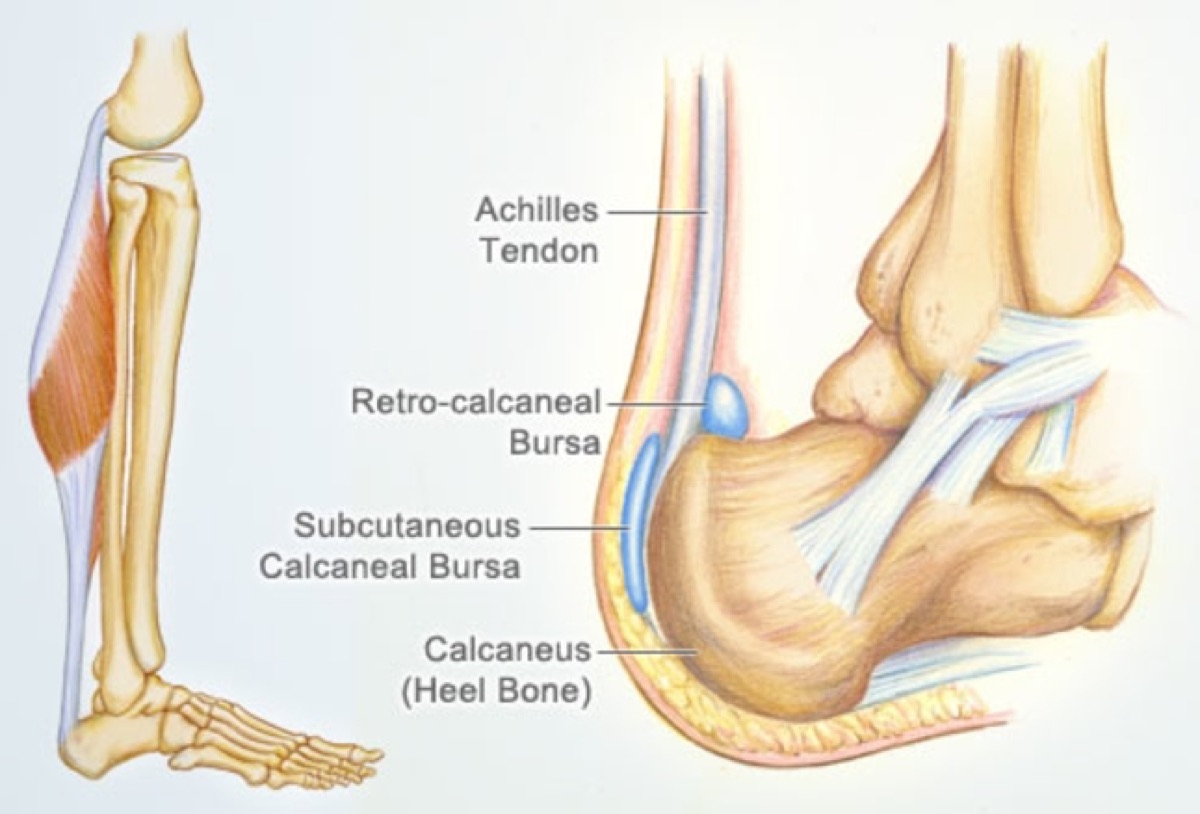

Haglund s Deformity and Other Causes of Heel Pain in Runners iRunFar

Haglund s Deformity Wheeless Textbook of Orthopaedics

Heel spur on shop back of heel